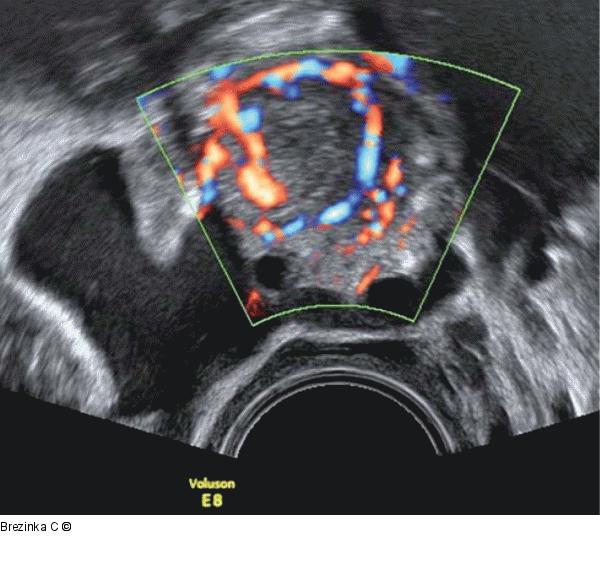

Abbildung 3: Gyn-Ultraschall Neben dem Ovar zeigt sich postovulatorisch Flüssigkeit im Douglas. Der Farbdoppler zeigt einen charakteristischen „ring of fire“, der das CL vom Rest des Ovars abgrenzt. |

Neben dem Ovar zeigt sich postovulatorisch Flüssigkeit im Douglas. Der Farbdoppler zeigt einen charakteristischen „ring of fire“, der das CL vom Rest des Ovars abgrenzt. |